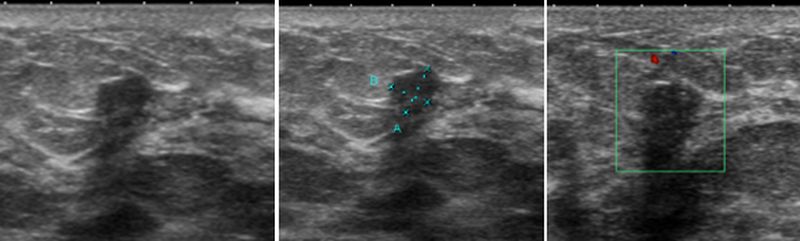

25歲年輕媽媽,母親為乳癌病患。因公司安排而接受健檢,在乳房超音波檢查下,發現左乳內下側有一個6×4.8mm大小的不規則狀結節,懷疑是纖維腺瘤或惡性腫瘤。經追蹤及切片證實為乳癌一期,因發現的早,及早手術切除,恢復良好。